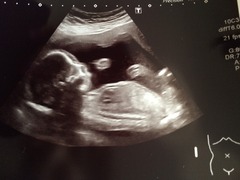

I've had a whirlwind of a day. Spent most of the morning in floods of tears as I fell over on my way to 20 week scan. There was something wet on the living room floor which I skidded on. Thank god I fell on my back rather than bump but it gave me a terrible fright and I was convinced I'd get bad news at hospital. Have attached 2 pics - second is very cute one of baby putting legs on head.

Luckily scan went really well and everything was absolutely fine. He refused to face the camera so I had a little walk and can of lemonade that got him moving! Will

Great pics Carla especially the legs on head one!! Congratulations on completing on the flat too. Sorry your not feeling great about it all. Maybe it's hormones playing a part. I'm sure it'll feel different once your in and it feels properly yours. Does it need work/decorating? X

Carla great scan pics. Glad all went well.

Carla congratulations on the flat and the scan. I always think big moments like that are never how I imagined they would be! Just think about how lovely it will be to be in the flat with your little baby in the summer Smile

Carla - lovely scan pics and congrats on house purchase. I totally know what you mean about no one sharing the good news tho and empty places are, well, empty. But a bit of ikea and eBay will do wonders as will a new day. my advice : house plants and tea lights all the way!

Carla lovely pic, congrats.